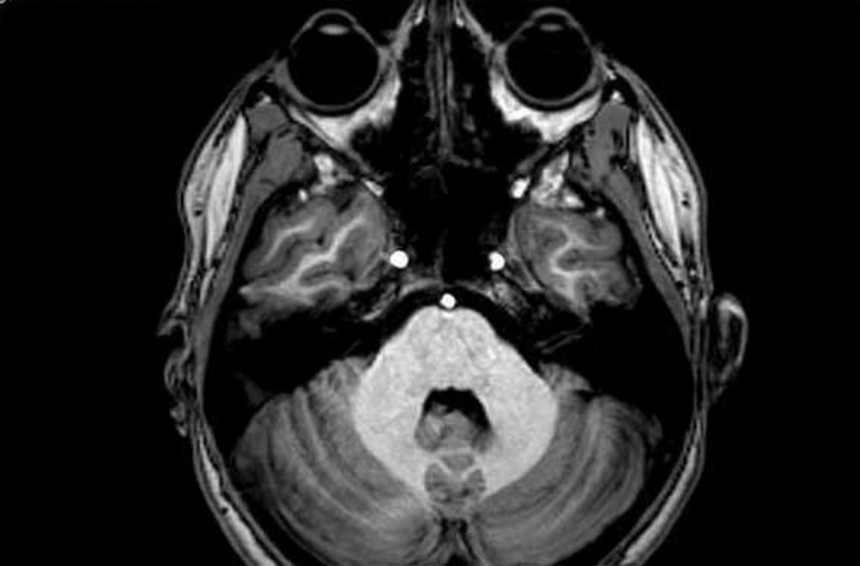

被験者がボタンを押す間、研究チームは、PETスキャンを使って被験者の脳の変化をモニタリングした。このPETスキャンは、大脳皮質全体のドーパミン・ニューロンの活性を追跡できるように修正をほどこしたものだ。それによって、ドーパミン作動性活性と、ひどく退屈な作業を続けようとする被験者の意志との間に、相関関係があるのかどうかを調べることができる。

この画像を大きなサイズで見るまず、左線条体と前頭前皮質腹内側部におけるドーパミン作動性活性が高い被験者の方が、そうでない被験者よりも報酬を得るために努力する意欲が高いことがわかった。

この画像を大きなサイズで見るさらに、今回の研究では、島(とう)皮質のドーパミン活性と、努力しようとする意欲との間には、逆の相関関係が存在するという驚くべき結果も明らかになった。

左線条体と前頭前皮質腹内側部の活性化により脳内に囁かれる「がんばって!継続は力なのよ!」という天使の声を、島皮質の活性化が「ああつまんない。続けても意味なくね?それより他に楽しいことしようよ」という悪魔の声でかき消していくのだという。島皮質のドーパミン作動性活性が高いほど、努力の苦しみはより顕著になり、そのせいで、われわれは努力をやめてしまうのだ。

この画像を大きなサイズで見る今回の研究結果により、「努力ができる人」というのは、「報酬が得られるかどうかわからない不確実な可能性」からも、ほんの少しだけど他の人より「快楽(左線条体と前頭前皮質腹内側部のドーパミン活性化)」を得ることができ、その一方で、自分の内なる「不満(島皮質のドーパミン活性化)」の声に鈍感でいられるという脳の働きをしているということが推測された。